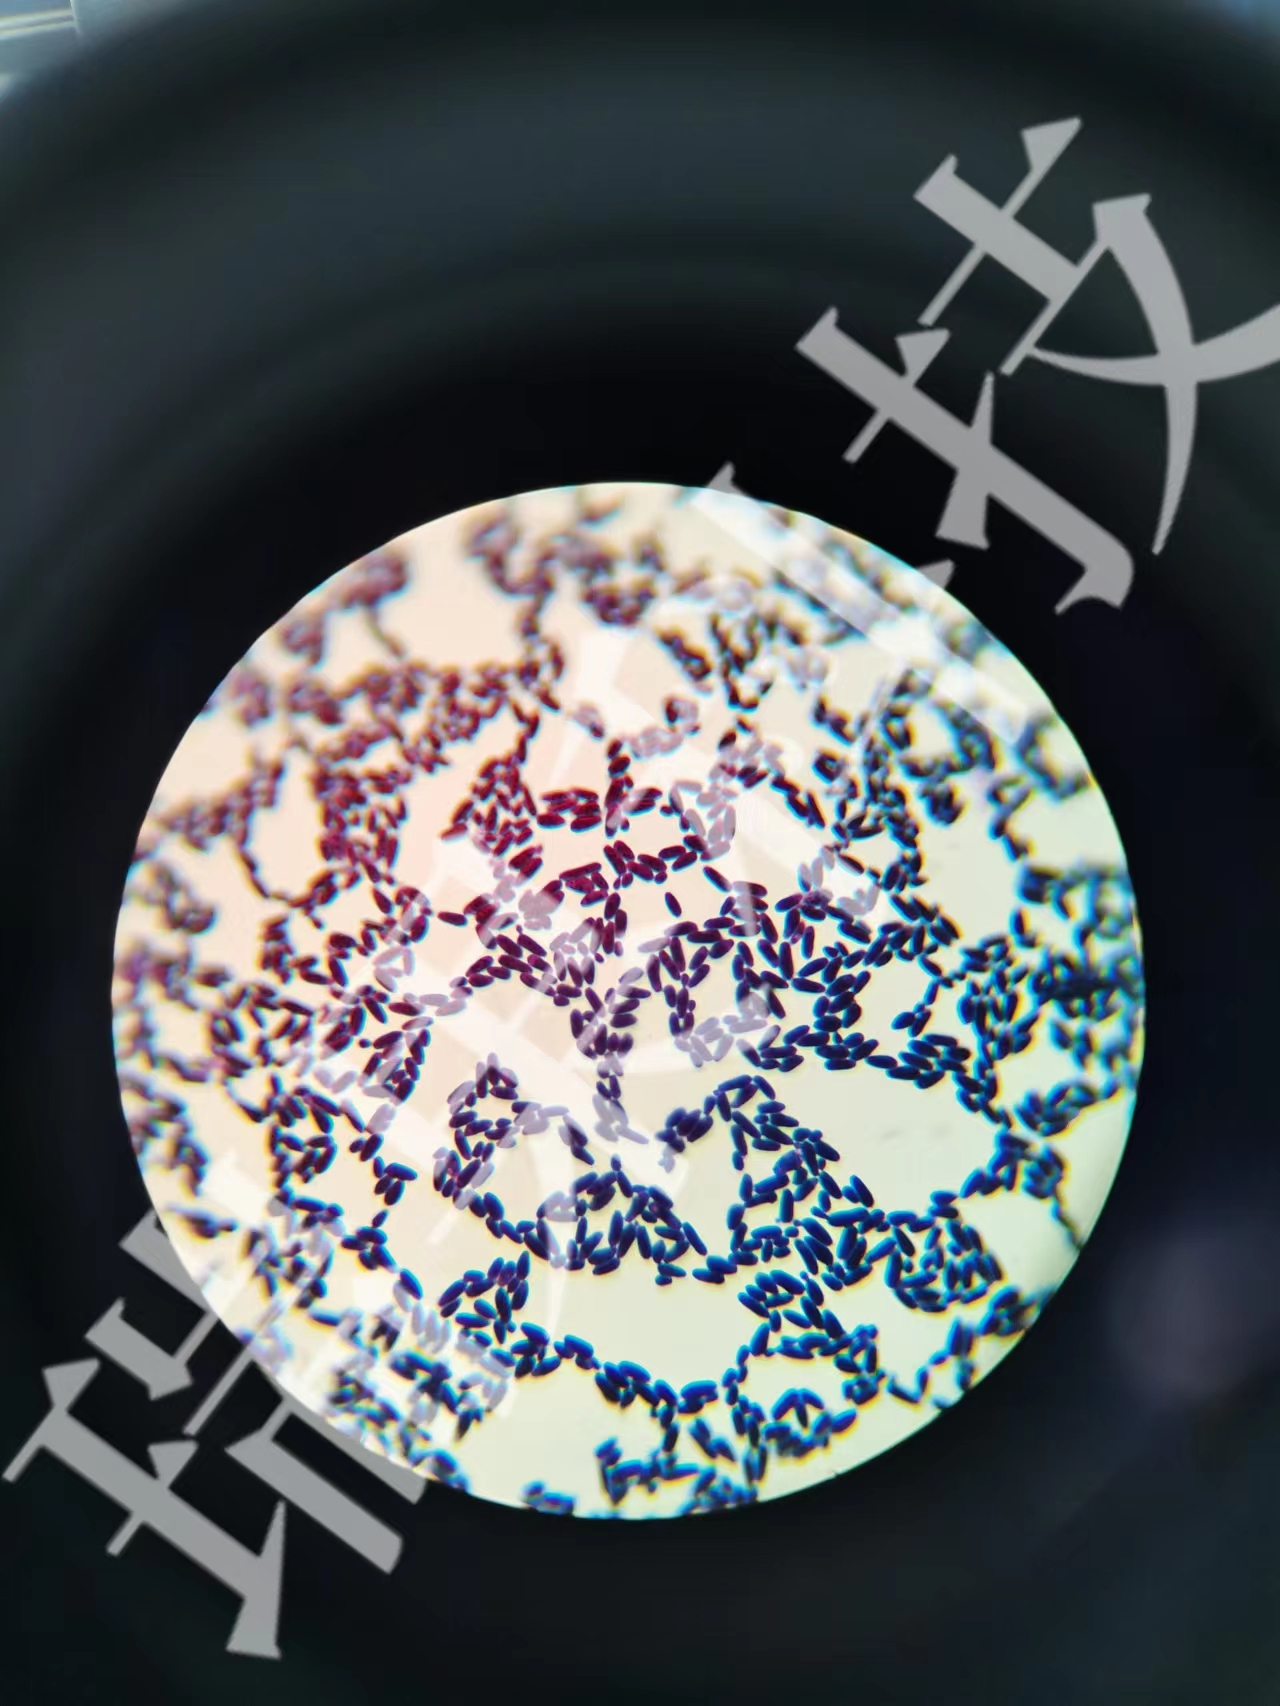

酵母菌革兰氏染色

酵母菌革兰氏染色 当前位置:首页 > 公司产品 > 产品服务 > 瑞果产品展示 > 细菌